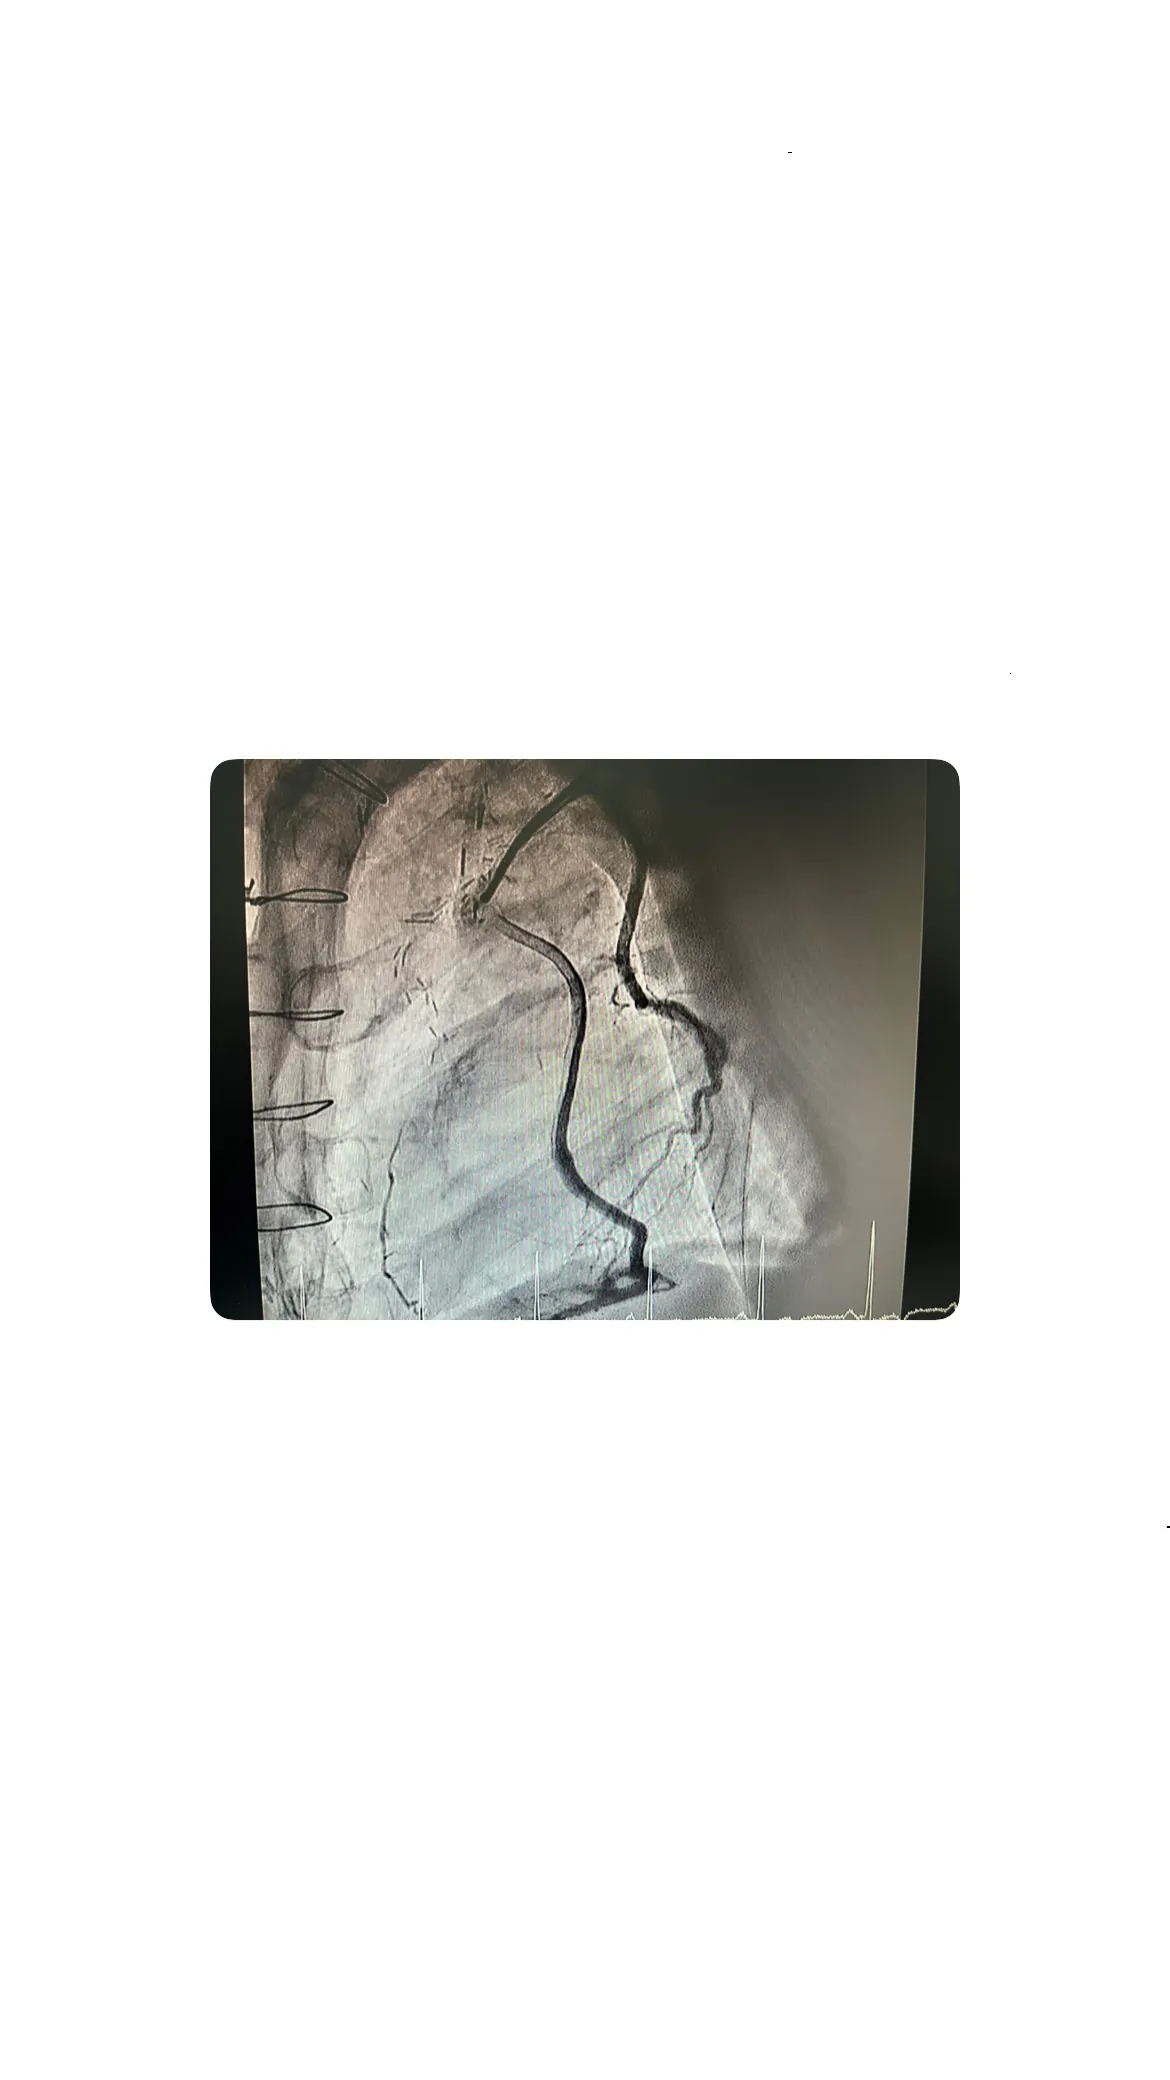

Revisión de los bypasses y situación de la coronaria derecha

Bypass a la coronaria derecha permeable

Además de evaluar el árbol coronario izquierdo, se revisó el estado del bypass a la coronaria derecha. Este bypass también estaba permeable, lo que significa que no había obstrucciones que impidieran el flujo sanguíneo. La funcionalidad de este bypass fue un factor positivo en la evaluación general del estado del paciente.

Distribución típica de los bypasses: mamaria y safena

En este caso, los bypasses seguían la distribución típica: la arteria mamaria se utilizó para la arteria descendente anterior (DEA), mientras que las venas safenas se emplearon para la coronaria derecha. Esta distribución es común en las cirugías de bypass y se elige por su eficacia en mejorar el flujo sanguíneo al corazón.